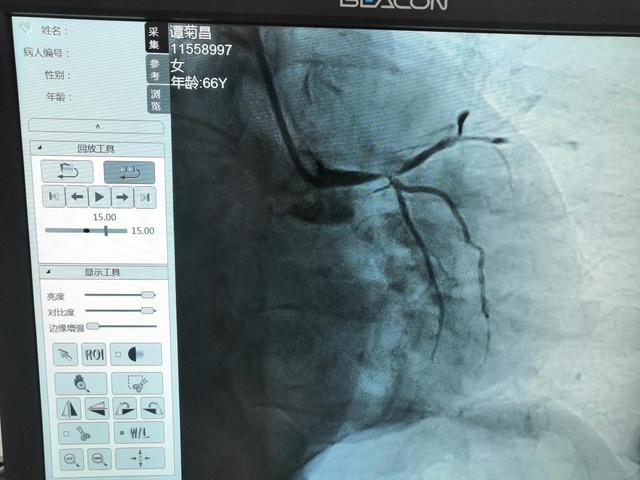

▼冠状动脉造影+支架植入术

(▲术前)

7月29日下午3点40分,66岁突发胸闷、胸痛患者转入急诊科,肢端循环差,情况危急,经医生紧急会诊,诊断为,冠状动脉粥样硬化性心脏病,急性广泛前壁及高侧壁ST段抬高型心肌梗死,患者命悬一线!通过与患者家属沟通,决定立即给予急诊冠状动脉支架植入(PCI)手术。

时间就是生命!术中患者生命垂危,医疗团队全力抢救,与死神赛跑。17点14分成功进行了血管开通,从患者同意到成功开通血管仅用了24分钟!